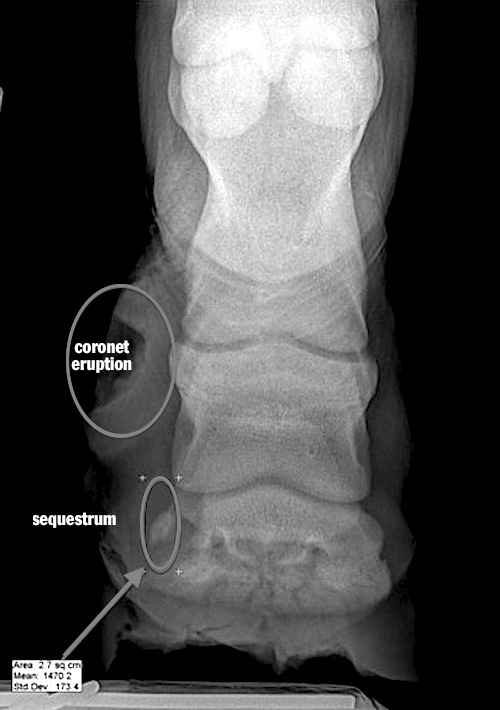

From hoofcare.blogspot.com

Fran Jurga`s Hoofcare + Lameness On the Case Foal Foot Bone Sequestrum Infection, Surgery and Coffin Joint Lameness Treatment Lameness is infrequent but may occur if infection, an abscess, or displacement of the coffin bone is also present. Low ringbone develops around the joint between the coffin bone and the short pastern bone, just within the top of the hoof wall. When ringbone affects the pastern or coffin joint, however, chronic lameness may result. Many cases of mystery lameness,. Coffin Joint Lameness Treatment.